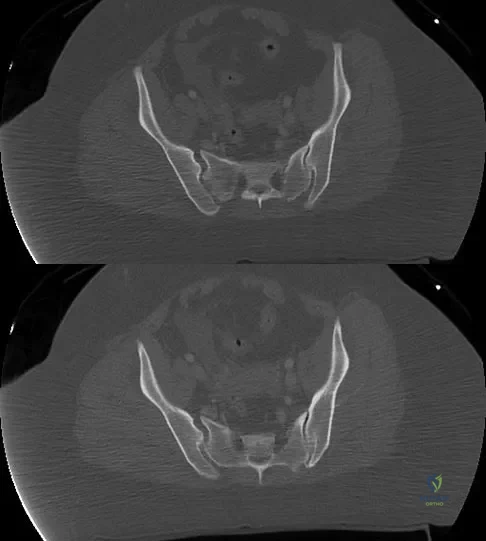

Question 48:

A 36-year-old woman was injured in a train derailment. She has a significant open depressed skull fracture with active bleeding, a hemopneumothorax, and blood in the left upper quadrant and colic gutter by Focused Assessment with Sonography for Trauma (FAST) examination. Additionally, she has the pelvic injury seen on the CT scans in Figures 18a and 18b. The mortality rate for this patient approaches

Options:

- less than 10%.

- 30%.

- 50%.

- 70%.

- greater than 90%.

Correct Answer: greater than 90%.

Explanation:

Mortality following trauma that requires surgical intervention for head, chest, and abdominal injury exceeds 90%. The type of pelvic fracture is a predictor of associated injury, blood requirements, and overall mortality. AP III pelvic fractures require the most blood, and are associated with significant abdominal trauma and shock. Lateral compression pelvic fractures are more associated with head, chest, and occasionally abdominal trauma, and mortality often occurs from associated injuries. Dalal SA, Burgess AR, Siegel JH, et al: Pelvic fracture in multiple trauma: Classification by mechanism is key to pattern of organ injury, resuscitative requirements and outcome. J Trauma 1989;29:981-1000. Eastridge BJ, Burgess AR: Pedestrian pelvic fractures: 5-year experience of a major urban trauma center. J Trauma 1997;42:695-700.